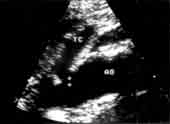

Рис. 5. УЗ-изображение атеросклеротической бляшки в устье чревного ствола. ТС-чревный ствол, АО-аорта.

.